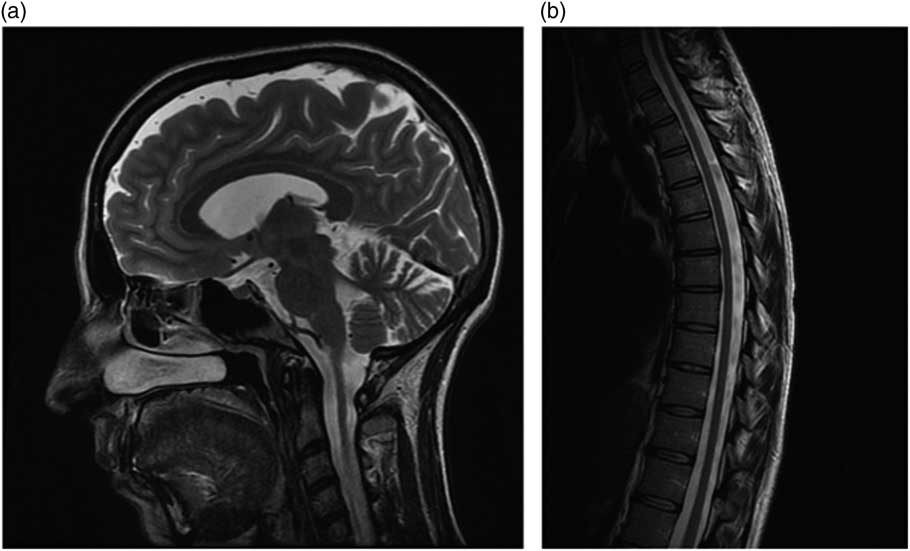

Neurological examination (see supplemental video) at the age of 34 years showed a clearly spastic gait with leg adduction and slight knee flexion. Ambulation was slow and possible only with unilateral support (a cane). The patient was not able to jump or run, or walk on her heels or toes. Her strength was significantly reduced (Medical Research Council grading 3+) and her muscle tone markedly increased in the lower but not in the upper limbs, whereas deep tendon reflexes were enhanced in the four limbs, with ankle clonus and bilateral Babinski signs. Proprioception and vibration sensation (ankle and knee) were also mildly reduced in the lower limbs. The cranial nerves were spared and she displayed neither nystagmus nor oculomotor abnormalities except for minimal fragmentation of smooth pursuit. Finger-to-nose and heel-to-knee tests were normal. Subjective imbalance was reported by the patient especially when changing direction and standing with eyes closed. The Romberg maneuver was, however, negative. The patient also experienced occasional urinary urgency. She showed no cognitive, language, or dysarthria, or skeletal abnormalities. Routine biochemistry, vitamin B12, vitamin E, venereal disease research laboratory test, chest radiograph, and electrocardiogram were also normal, although persistently high levels of serum iron were found. Her Spastic Paraplegia Rating Scale Annex 1 (SPRS) score was 23/52 and her Scale for Assessment and Rating of Ataxia score was 3/40 (only gait and stance). Brain magnetic resonance imaging (MRI) (Figure a), at age 34 years, displayed slight enlargement of the pericerebellar spaces in both the vermis and the hemispheres, whereas a spine MRI (Figure b) showed questionable cervical cord atrophy and some thinning of the dorsal tract. Motor evoked potentials showed delayed central conduction time. Peripheral nerve conduction studies, and visual and brainstem evoked potentials were all unremarkable. Heart (echocardiogram) and retinal investigations (optical coherence tomography examination) were also normal.

Figure Brain (a) and spine (b) MRI features in the patient.

Atypical presentations, such as the one we observed in our patient, who showed a progressive spastic paraparesis without gait or limb ataxia, are rare in large FRDA series,Reference Parkinson, Boesch, Nachbauer, Mariotti and Giunti 4 usually related to late-onset and smaller GAA1 size, and difficult to diagnose without a positive family history. A few similar cases have been described previously in the literature, prior to the identification of the first SPG genes,Reference Finsterer, Löscher, Quasthoff, Wanschitz, Auer-Grumbach and Stevanin 1 including a spastic variant of the Acadian form of FRDA described in the early 1980s.Reference Barbeau, Roy, Sadibelouiz and Wilensky 5 With hindsight, the spinal cord thinning, together with the slight enlargement of the cerebellar sulci observed in our patient, might have been taken as “red flags” pointing to a variant of FRDA and making it possible to avoid time-consuming analyses of several HSP genes.